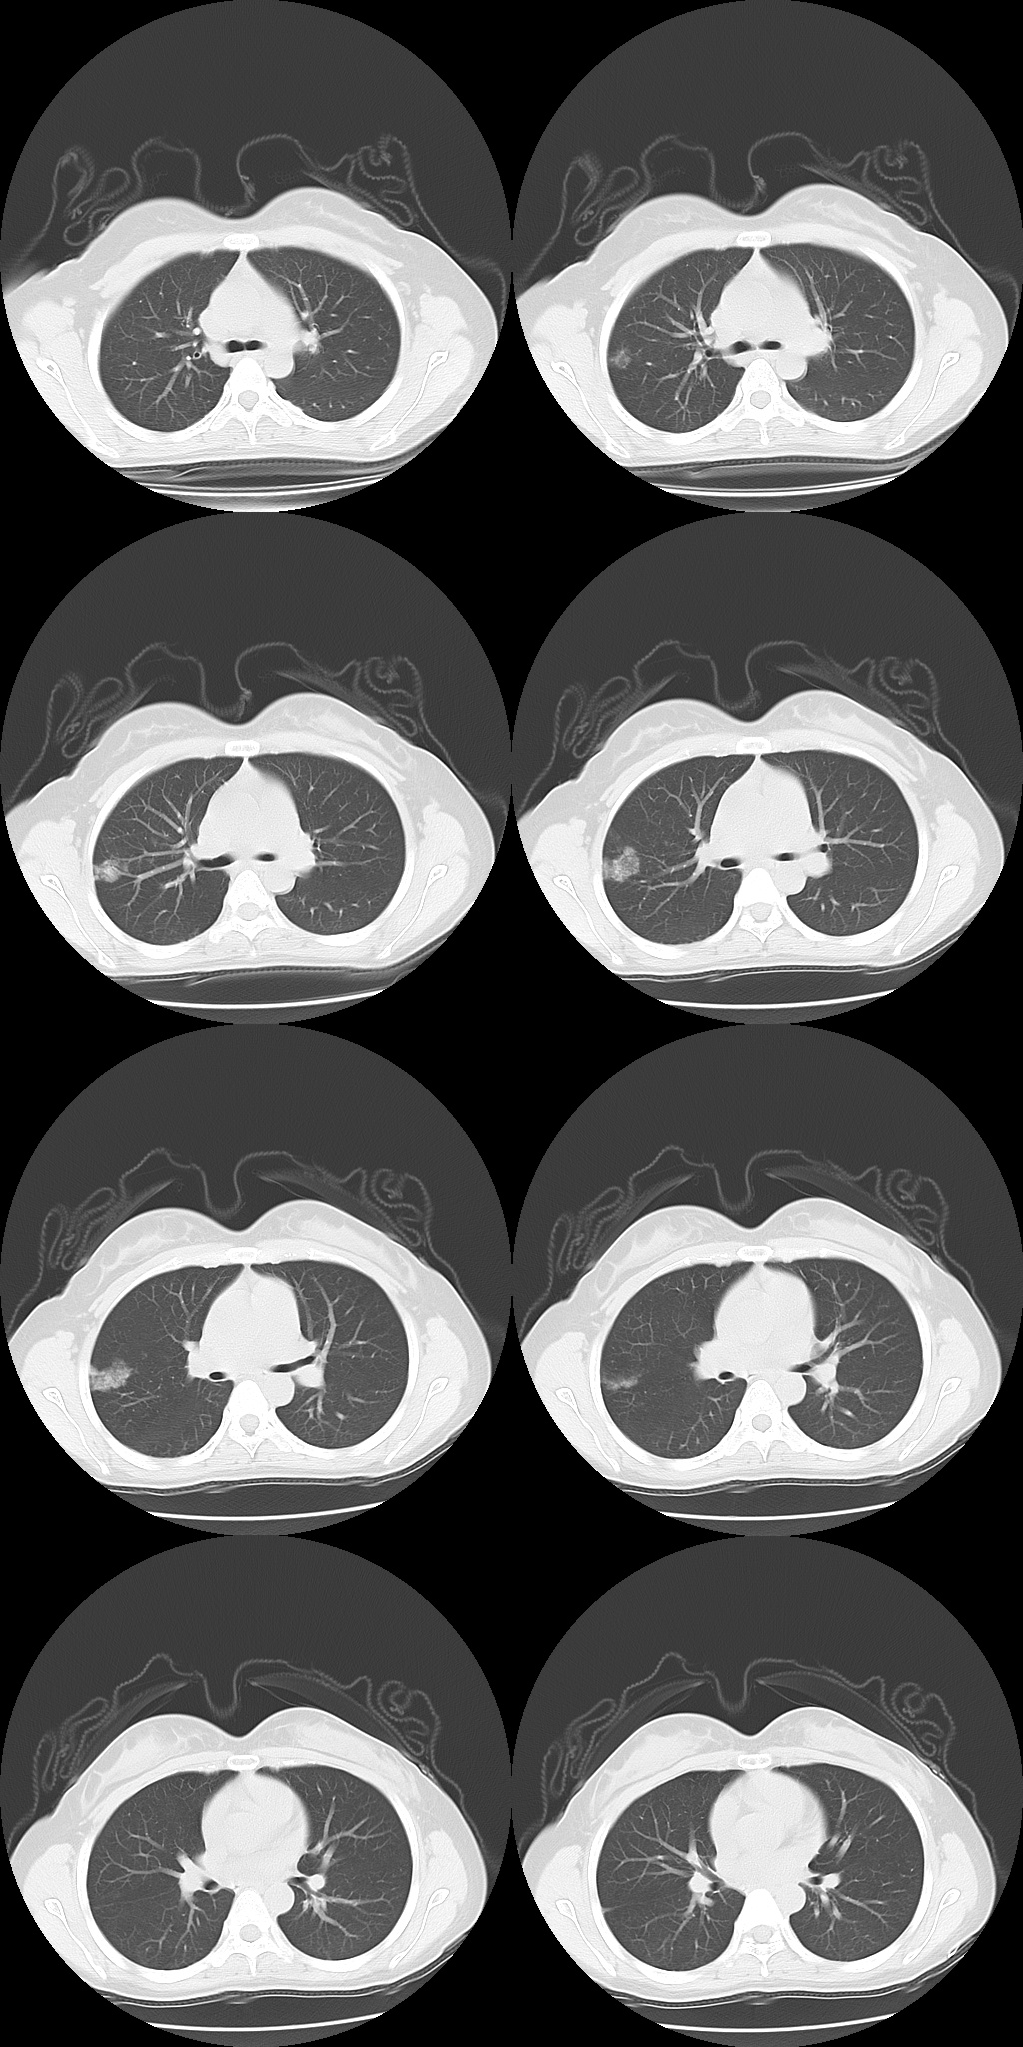

X 线、CT 平扫表现为类似肺炎的渗出性病变或轮廓清楚的肺内结节、胸腔积液、薄壁囊肿 (腔) 或肺大疱及气胸等征象,有的出现支气管阻塞和周围肺不张。如相同肺段在两次经期出现类似肺内改变,而月经期后肺内无异常发现或咯血停止,在排除其他肺部疾病后,可确诊。

患者月经期结束后一周复查 CT